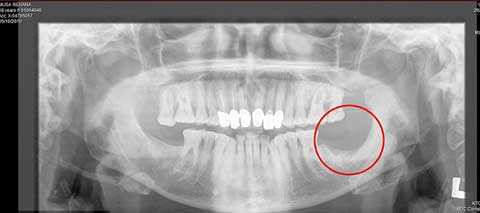

Trước khi đi nhổ răng, bà Musa đã cẩn thận tới Bệnh viện Derbyshire Royal để kiểm tra, các bác sĩ ở đây sau khi làm lành vết thương ở má của bà cũng khuyên bà nên nhổ chiếc răng khôn để tránh làm tổn thương cho má. Các bác sĩ đã viết sơ lược về tiền sử bệnh của bà để bác sĩ nha khoa sẽ lưu ý trước khi nhổ răng.

Vài ngày sau khi nhổ răng, bà bắt đầu bị những cơn đau nhức liên tục hành hạ. Vết thương trong chỗ nhổ không thể tự lành được mặc dù bà đã phải dùng rất nhiều phương pháp giúp làm lành, thậm chí cả một phần xương hàm của bà cũng được bỏ đi để giúp bà thoát khỏi sự đau nhức do vết thương nhổ răng để lại.